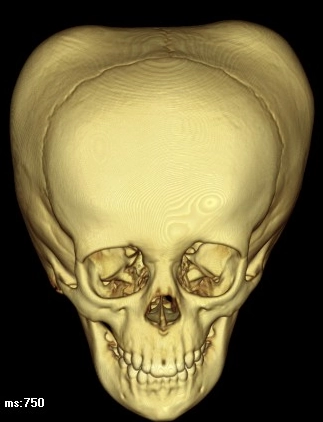

Thoát vị não (Brain herniation)

Thoát vị não ra ngoài sọ (Extracranial Brain Herniation)